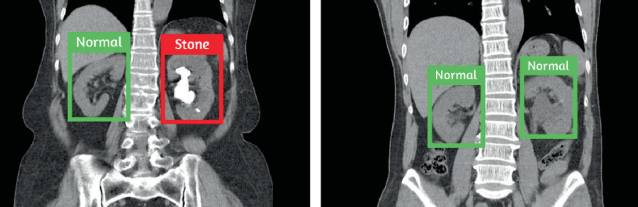

Kidney Stone Detection

Our AI system analyzes medical images to detect kidney stones with high accuracy, aiding in quick diagnosis and treatment planning.

Kidney Stone Image